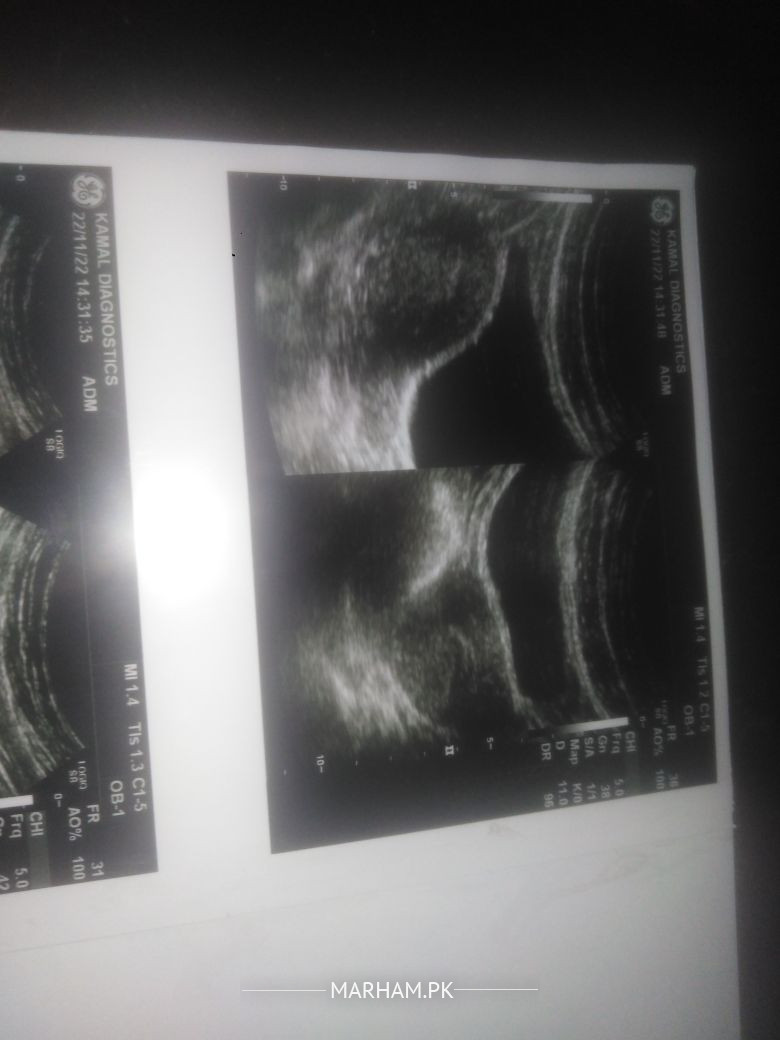

Only asking from Gynecologist kindly m ny apni reports share ki hien is k about btye ga pregnancy continue ho skti ha ya ni B ultrasound m gastational sac 29.1mm ai ha gas age7 weeks ha aur doppler ultrasound ki report b attach ki hien